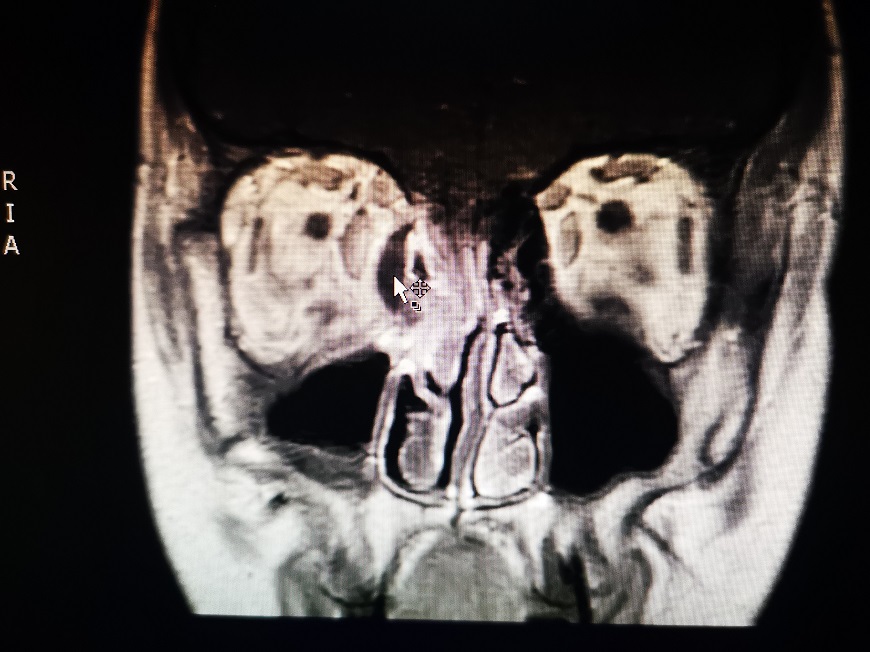

Το απόστημα της οφθαλμικής κοιλότητας (υποπεριοστικό απόστημα) είναι μια επείγουσα και ιδιαίτερα επικίνδυνη επιπλοκή μετά από οξεία φλεγμονή των παραρρινίων κόλπων (παραρρινοκολπίτιδα) η οποία μπορεί να οδηγήσει μέσα σε λίγες ώρες σε μόνιμες βλάβες του οφθαλμού και χρειάζεται επείγουσα χειρουργική αντιμετώπιση.

Οι ενδοσκοπικές επεμβάσεις των παραρρινίων κόλπων είναι ελάχιστα τραυματικές για τον ασθενή μια και αποφεύγονται οι εξωτερικές τομές, είναι όμως δύσκολες λόγω της πολύπλοκης ανατομίας της περιοχής οποία είναι ξεχωριστή στον κάθε ασθενή, και των ιδιαίτερα σημαντικών δομών που βρίσκονται πολύ κοντά (μάτια, εγκέφαλος). Συγκεκριμένα σε ασθενείς με κορονοϊό η συγκεκριμένη επέμβαση θεωρείται υψηλού κινδύνου για την επιμόλυνση του προσωπικού, λόγω παραγωγής αερολύματος.